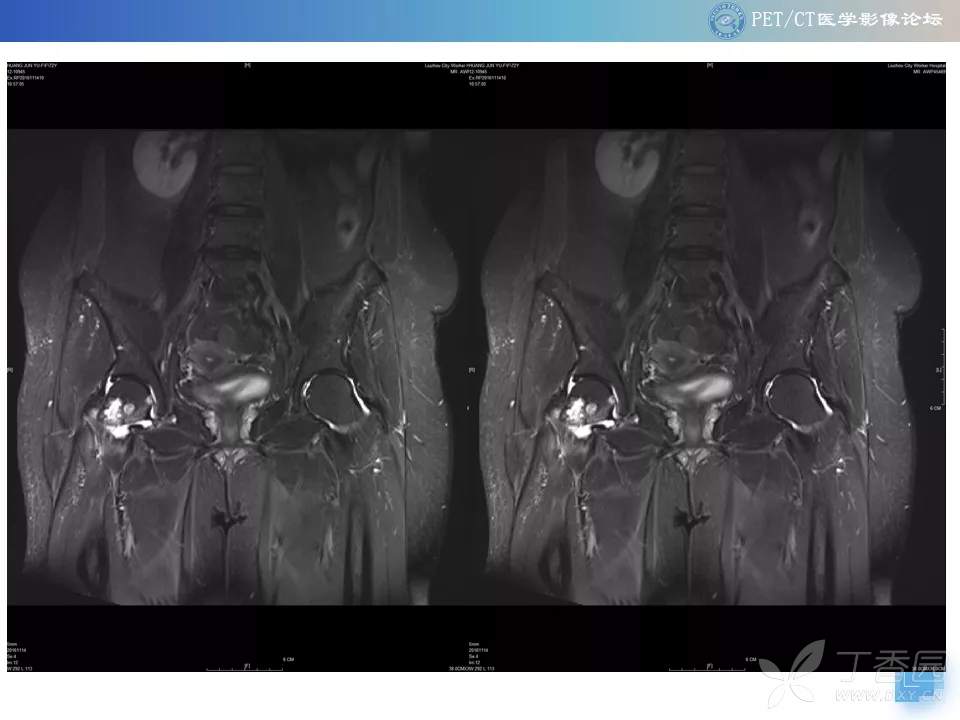

【PET/CT 病例读片】髋关节占位性病变

注:病例来源【PETCT病例读片第二十二期】

查看病例结果及诊断分析请关注公众号【PETCT医学影像论坛】